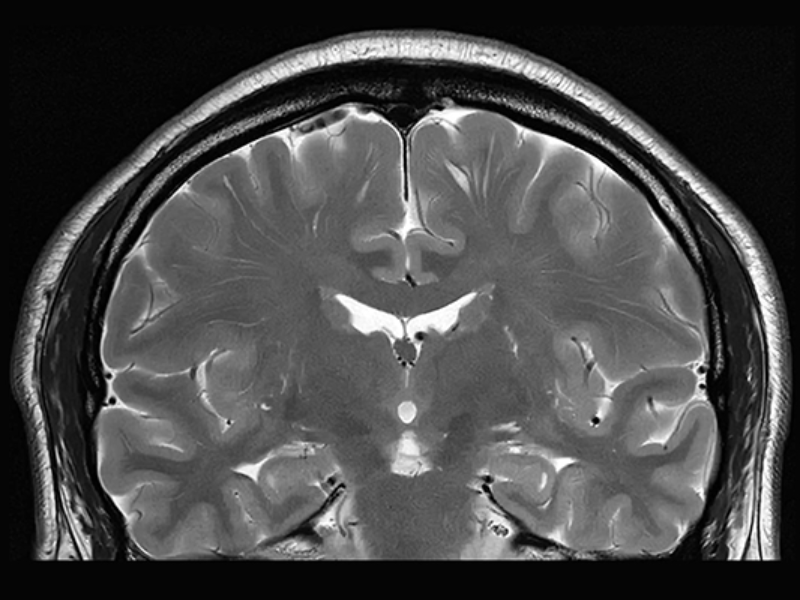

T2 Brain with uAI DeepRecon

uAI DeepRecon

uAI DeepRecon provides an increase in both signal and resolution at the time of scanning or during post reconstruction using a convolutional neural network trained model.